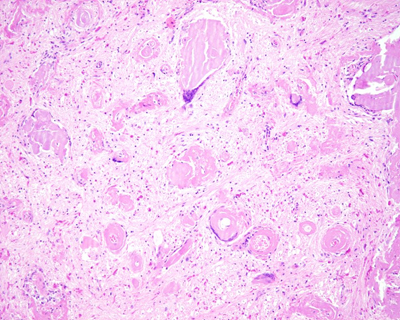

Another interesting result of brain research was a case of a young male with paranoid schizophrenia, who developed bulbar symptoms and died in his sleep. A few months before death, he was diagnosed by MRI as having multiple sclerosis. The brain cutting revealed that he had light chain deposition disease (LCDD) brain vasculopathy with multifocal hypoxic brain injury, especially prominent and fatal in the medulla (Figure 15). When we submitted the manuscript to the journal Human Pathology, it was the first case of LCDD restricted to the brain [24]. By the time of publication, however, the first published case of LCDD restricted to the brain had been published by Fischer et al. [25]

Figure 15. Severe light chain deposition disease vasculopathy (LCDDV) of medulla. H&E, original magnitude 40x.